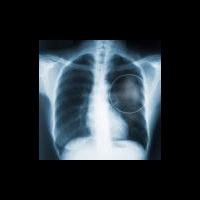

Вакцина против немелкоклеточного рака легкого увеличивает продолжительность жизни

Разработана вакцина, увеличивающая выживаемость пациентов с немелкоклеточным раком легкого. На ежегодном собрании Американской ассоциации исследований в области онкологии (American Association for Cancer Research) были представлены результаты исследования вакцины, применяемой при немелкоклеточном раке легкого – препарата белагенпуматуцела.

Исследователи отмечают значительное улучшение показателей долгосрочной выживаемости пациентов с немелкоклеточным раком легкого.

Исследование проводилось на протяжении 5 лет. В исследовании приняли участие 75 больных с немелкоклеточным раком легкого на различных стадиях.

Известно, что при немелкоклеточном раке легкого пятилетняя выживаемость составляет 11–15%. У больных с метастатическим немелкоклеточным раком легкого третьей стадии или четвертой стадии 5-летняя выживаемость составляет не более 5%.

В ходе клинических испытаний исследователи пришли к заключению, что применение белагенпуматуцела способствует повышению 5-летней выживаемости больных немелкоклеточным раком легкого до 20%, при третьей стадии заболевания и метастазах и при четвертой стадии 5-летняя выживаемость составляет около 18%.

Исследование показателей активации иммунного ответа (гуморального и клеточного звена иммунного ответа) при использовании вакцины белагенпуматуцел показало, что уровень активации иммунной защиты сопряжен с показателем 5-летней выживаемости. Определение уровня активации иммунного ответа может применяться для прогнозирования результатов лечения.

Вакцина белагенпуматуцела создана на основе 4 генно-модифицированных клеточных линий, продуцирующих антисмысловую РНК к трансформирующему фактору роста β2 (Тransforming Growth Factor beta2, TGFβ2). Вакцина снижает способность опухолевых клеток подавлять иммунную систему организма и активизирует защитные силы организма.